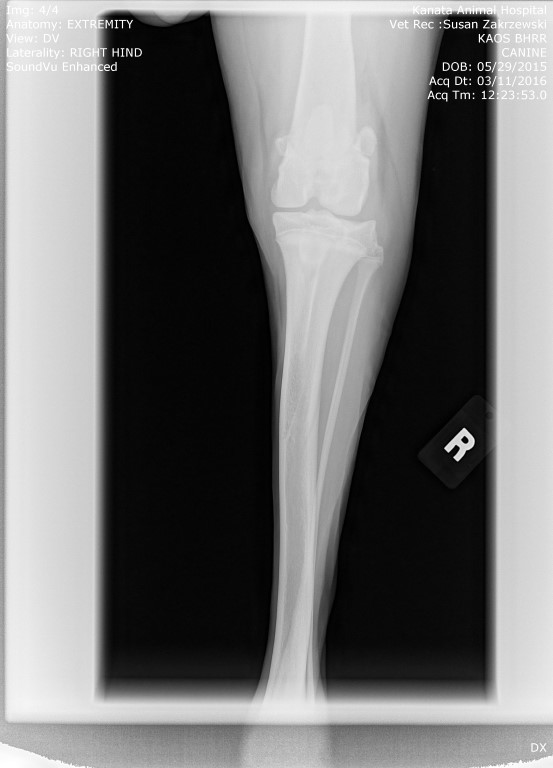

Please and thank you again on behalf of the Great Dane puppy that came to us at 6 weeks of age with a broken leg…..and, then diagnosed that he also has a knee concern.

For those who are also not yet aware, BHRR’s Kaos is cyptorchid which shall make his neutering more expensive and complex. Poor baby. 🙁 Let’s hope that the second testicle is just under the skin.